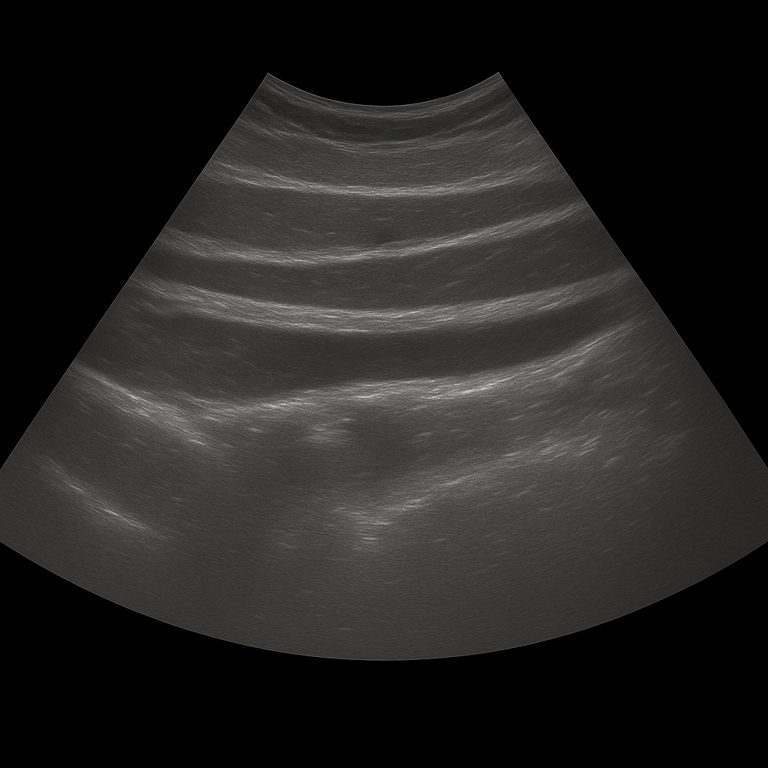

An abdominal ultrasound is used to examine the skin, subcutaneous tissue and muscles of the abdominal wall. The examination is performed by a specialist in radiology and provides detailed images in real time that can show changes that cause pain, swelling or visible bulges in the abdomen. Abdominal ultrasound is often used when there is suspicion of hernia, fluid accumulation, hematoma or other changes in the soft tissues.

Unlike MRI and CT, which are used to map deeper organs and structures in the abdominal cavity, ultrasound is the first choice for examining superficial changes in the abdominal wall. Ultrasound shows muscles, tissue layers and possible defects in real time - without radiation or contrast media.

The examination is performed while you lie on your back. A gel is applied to the skin and the doctor moves the ultrasound probe over the area where you are experiencing discomfort. The abdominal wall is examined in different planes, both at rest and under slight tension, which makes it possible to see any hernias or defects that appear when the abdomen is loaded.